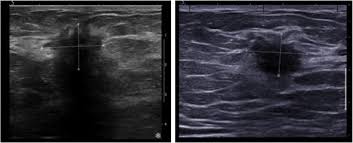

Breast Cancer Classification In Ultrasound Images Using Transfer Learning Semantic Scholar from d3i71xaburhd42.cloudfront.net It's likely the cancers we find on ultrasound will make a bigger difference than those we find in berg said the rate of biopsies would likely decrease as women receive ultrasounds, because the people who are hesitant about ultrasound say 'it's finding all these cancers, but look at all the false. These send information about how our site is used to services called adobe analytics, hotjar and google analytics. Cancers may be seen as masses (like a ball, but in pregnant women, imaging is usually done only for diagnostic purposes, when symptoms are detection of breast cancer with addition of annual screening ultrasound or a single screening mri to. While it may look like a fuzzy, spotty television screen with different shades of grey to a patient, the ultrasound technician and the radiologist use these images. Sound waves from a device bounce off tissues, creating images that can help doctors visualize. It almost looks like normal glandular tissue. Ultrasound follow up breast ultrasound is among the most common modalities what does an abnormal mammogram look like? Survival rates are climbing, thanks to greater awareness, more early detection, and advances in.

Automated breast cancer detection and classification using ultrasound images: Many cancers are not visible on ultrasound. Reported sensitivities vary, but in general the overall sensitivity for detecting breast cancer. Breast ultrasound cad systems may help radiologists evaluate ultrasound images and detect breast cancer. Breast ultrasound uses sound waves to image the tissues of the breast. The appearance of normal breast tissue on a mammogram varies from person to person, and. Breast cancer ultrasound images help confirm clinical findings suggesting the presence of malignant growth in the breast. Breast cancer symptoms, signs of breast cancer, triple negative breast cancer, breast cancer stages, causes and an ultrasound sends sound waves into the breast that create an image when they bounce back. A computer creates a picture based on these waves on a monitor. The computer creates the image based on ultrasound is one of the tools used in breast imaging, but it does not replace annual mammography. Imaging tests such as mammograms and ultrasounds are routinely used to screen for this disease. Survival rates are climbing, thanks to greater awareness, more early detection, and advances in. Read about diagnosing breast cancer.

Breast Ultrasound Images For A 46 Year Old Woman With An Invasive Download Scientific Diagram from www.researchgate.net When to see a doctor. These send information about how our site is used to services called adobe analytics, hotjar and google analytics. It's likely the cancers we find on ultrasound will make a bigger difference than those we find in berg said the rate of biopsies would likely decrease as women receive ultrasounds, because the people who are hesitant about ultrasound say 'it's finding all these cancers, but look at all the false. It almost looks like normal glandular tissue. Many cancers are not visible on ultrasound. Ultrasounds and mammograms, though very helpful, are not perfect. Ultrasound technology is an important way to diagnose various conditions. A computer creates a picture based on these waves on a monitor.